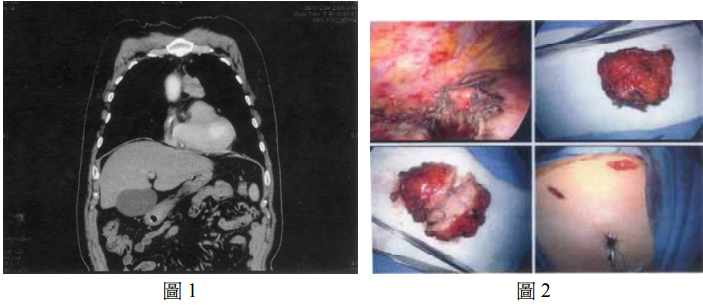

53 一位 50 歲男性,無明顯症狀,依影像檢查如下圖 1 及手術圖如下圖 2,選出最合適之敘述?

(A)腫瘤位於後縱隔腔 (B)發生於此處最常見之腫瘤為淋巴瘤 (C)病人可能會有肌肉無力症狀 (D)此病人若無症狀可觀察追蹤